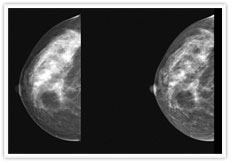

Patient Care Community Breast Cancer. 3D mammography is a revolutionary new screening and diagnostic tool designed for early breast cancer detection that can be done in conjunction with a traditional 2D digital mammogram. 13001 East 17th Place Aurora CO 80045.

Reviews 720 848-1030 Website. Breast Tomosynthesis 3D Mammography UC Health breast imaging facilities use an advanced breast imaging tool called 3D mammography. The Breast Imaging section is located in the University of Colorado Breast Center a multidisciplinary breast center at the Anschutz Outpatient Pavilion AOP incorporating breast imaging breast surgery breast oncology internal medicine genetic counseling and specialized nursing.